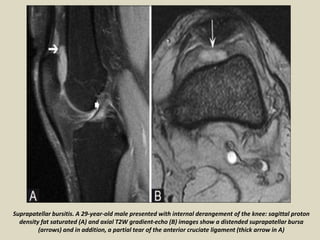

Suprapatellar bursitis. A 29-year-old male presented with internal derangement of the knee: sagittal proton

density fat saturated (A) and axial T2W gradient-echo (B) images show a distended suprapatellar bursa

(arrows) and in addition, a partial tear of the anterior cruciate ligament (thick arrow in A)